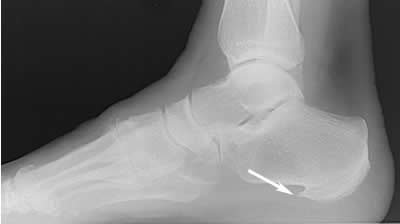

Лечение пяточных остеофитов

Лечение пяточных остеофитов 118 фото